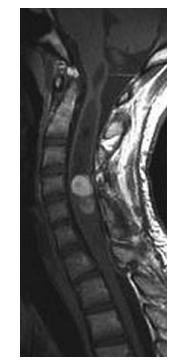

Which one of the following is most likely based on the T2-Weighted MRI shown below?

a. Ependymoma

However, studies have shown that ependymomas

have a predilection for the caudal spinal cord,

with 50% of ependymomas arising in the lumbosacral cord or filum terminale and the remaining 50% occurring nonpreferentially along the cervical or thoracic spinal cord. On imaging, anaplastic ependymomas may be distinguished by their larger size, numerous cysts, and heterogeneous postcontrast enhancement. Anaplastic ependymomas are uncommon, comprising only 5% of all ependymomas, but they are characterized by anaplastic features (i.e. vascular proliferation, mitotic figures, cellular pleomorphism, and necrosis) on histologic analysis. Patients experience higher rates of tumor recurrence and decreased rates of survival. Classic radiographic features of spinal cord ependymomas include distinct tumor-spinal cord border, an associated syrinx, cysts within or adjacent to the mass, and hemosiderin deposits or “caps” near the poles of the tumor on T1 and T2. The treatment of

choice is gross total surgical resection.